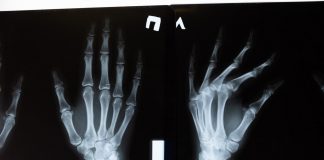

Tag: badanie rentgenowskie

RTG, czyli badanie rentgenowskie, to jedna z popularniejszych, a zarazem najstarszych metod obrazowania. Ma szerokie zastosowanie diagnostyczne – pozwala wykryć zmiany pourazowe, zapalne, zwyrodnieniowe...